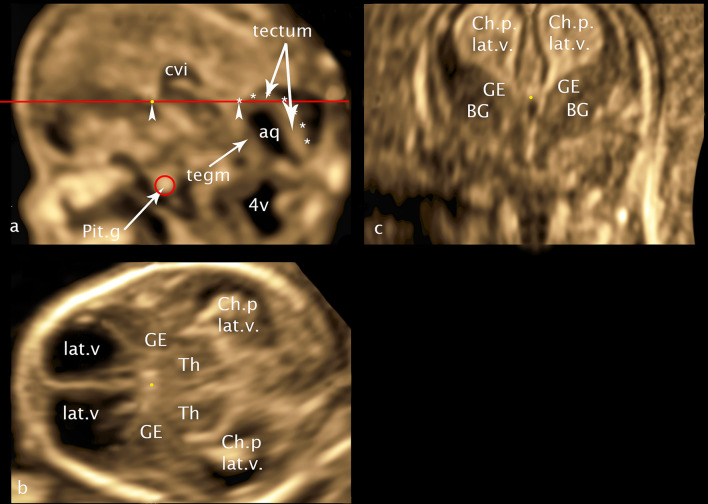

For a better orientation in the fetal brain the midsagittal plane through the choroid plexus of the 3rd ventricle and pituitary gland was used as a reference plane in multiplanar mode additionally supplemented by a line from the inferior border of the choroid plexus of the 3.v to the cranial border of tectum serving as the horizontal orientation (Fig. 1a). Fixing this plane creates a grid of planes parallel and perpendicular to each other as a result of the multiplanar mode, which allows reproducible measurements. We will use this system of parallel and rectangular planes in our paper to further specify already defined planes on the one hand and to define a new plane on the other hand.

Fig. 1.

CRL 60.1 mm a midsagittal plane b axial plane c coronar plane: yellow point—marker dot; red circle—pituitary gland; red line—horizontal orientation line; arrowheads—orientation points for the horizontal alignment—inferior border of choroid plexus and cranial border of tectum at the entrance of the aqueduct; asterisk—cranial border of the tectum; cvi—cavum velum interpositum; aq—aqueduct; 4v—fourth ventricle; Pit.g—Pituitary gland; tegm—tegmentum; Ch.p. lat.v.—choroid plexus lateral ventricle; GE—ganglionic eminence; BG—basal ganglia: lat.v—lateral ventricle; Th—thalamus

For the presentation and measurement of GE and BG in coronal view we used the transcaudate plane (Fig. 1c) (Volpe et al. 2021; Malinger et al. 2020) with choroid plexus of the third ventricle between the foramina of Monro as reference point, similarly in axial view a new transchoroidal plane (Fig. 1b) was defined using choroid plexus of the 3rd ventricle as craniocaudal reference point. For the measurement of the thalamus lateral and thalamus/hypothalamus (Th/HyT) in coronal view transthalamic plane (Volpe et al. 2021; Malinger et al. 2020) was used. For this purpose, in the grid described above, the coronal plane was moved directly behind the caudal end of the cerebral stalk.